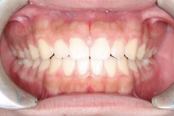

症例 ②

●空隙歯列を伴う開咬

●前歯を後ろに下げるために必要な隙間が存在している

- 治療後 -

▶︎隙間を閉じながら上下前歯を後ろに下げ、開咬の改善を行いました。